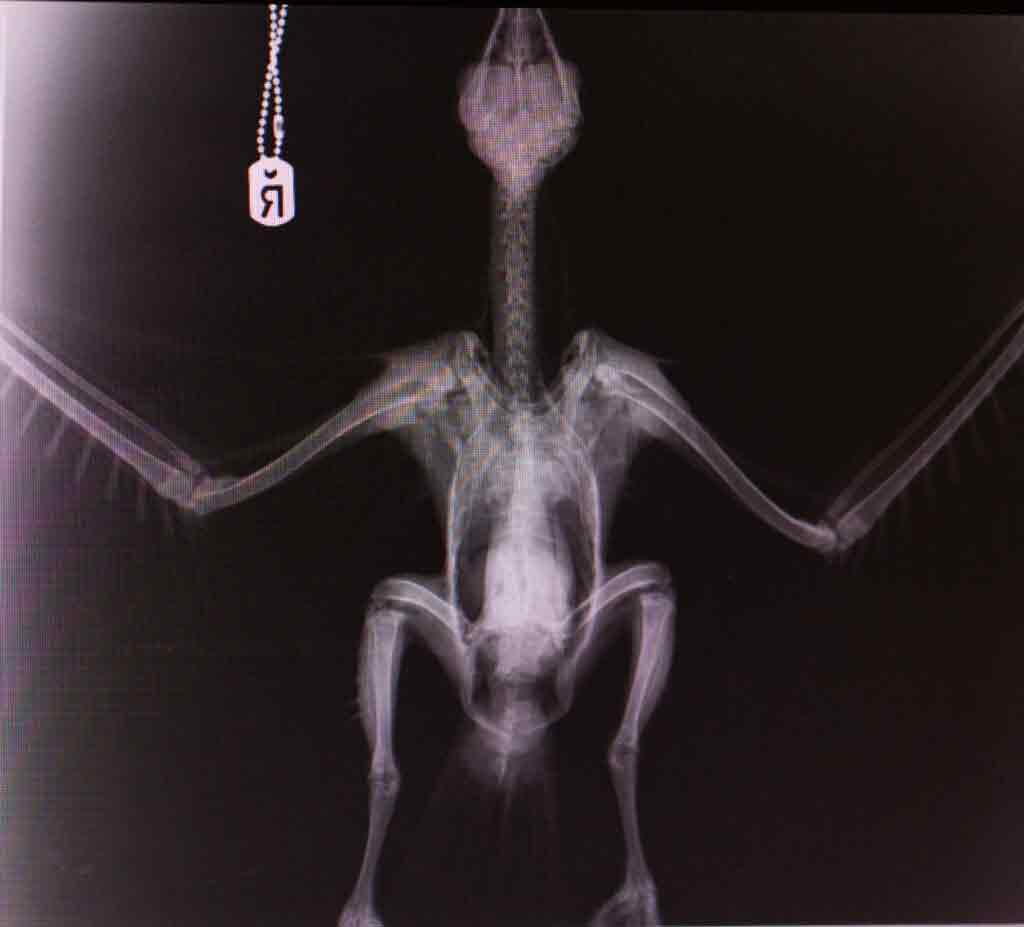

Other than the lesion to his mouth, Mr kite had no other obvious reasons for being grounded, an x-ray ruled out anything sinister, but when he was placed in to an aviary he showed little to no interest in taking flight.